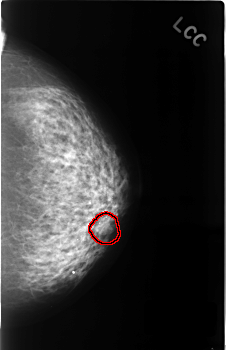

C_0419_1.LEFT_CC

LEFT_CC LINES 4544 PIXELS_PER_LINE 2936 BITS_PER_PIXEL 12 RESOLUTION 50 OVERLAY

FILE: C_0419_1.LEFT_CC.OVERLAY

TOTAL_ABNORMALITIES 1

ABNORMALITY 1

LESION_TYPE MASS SHAPE ROUND MARGINS ILL_DEFINED

ASSESSMENT 3

SUBTLETY 3

PATHOLOGY BENIGN_WITHOUT_CALLBACK

TOTAL_OUTLINES 1

BOUNDARY